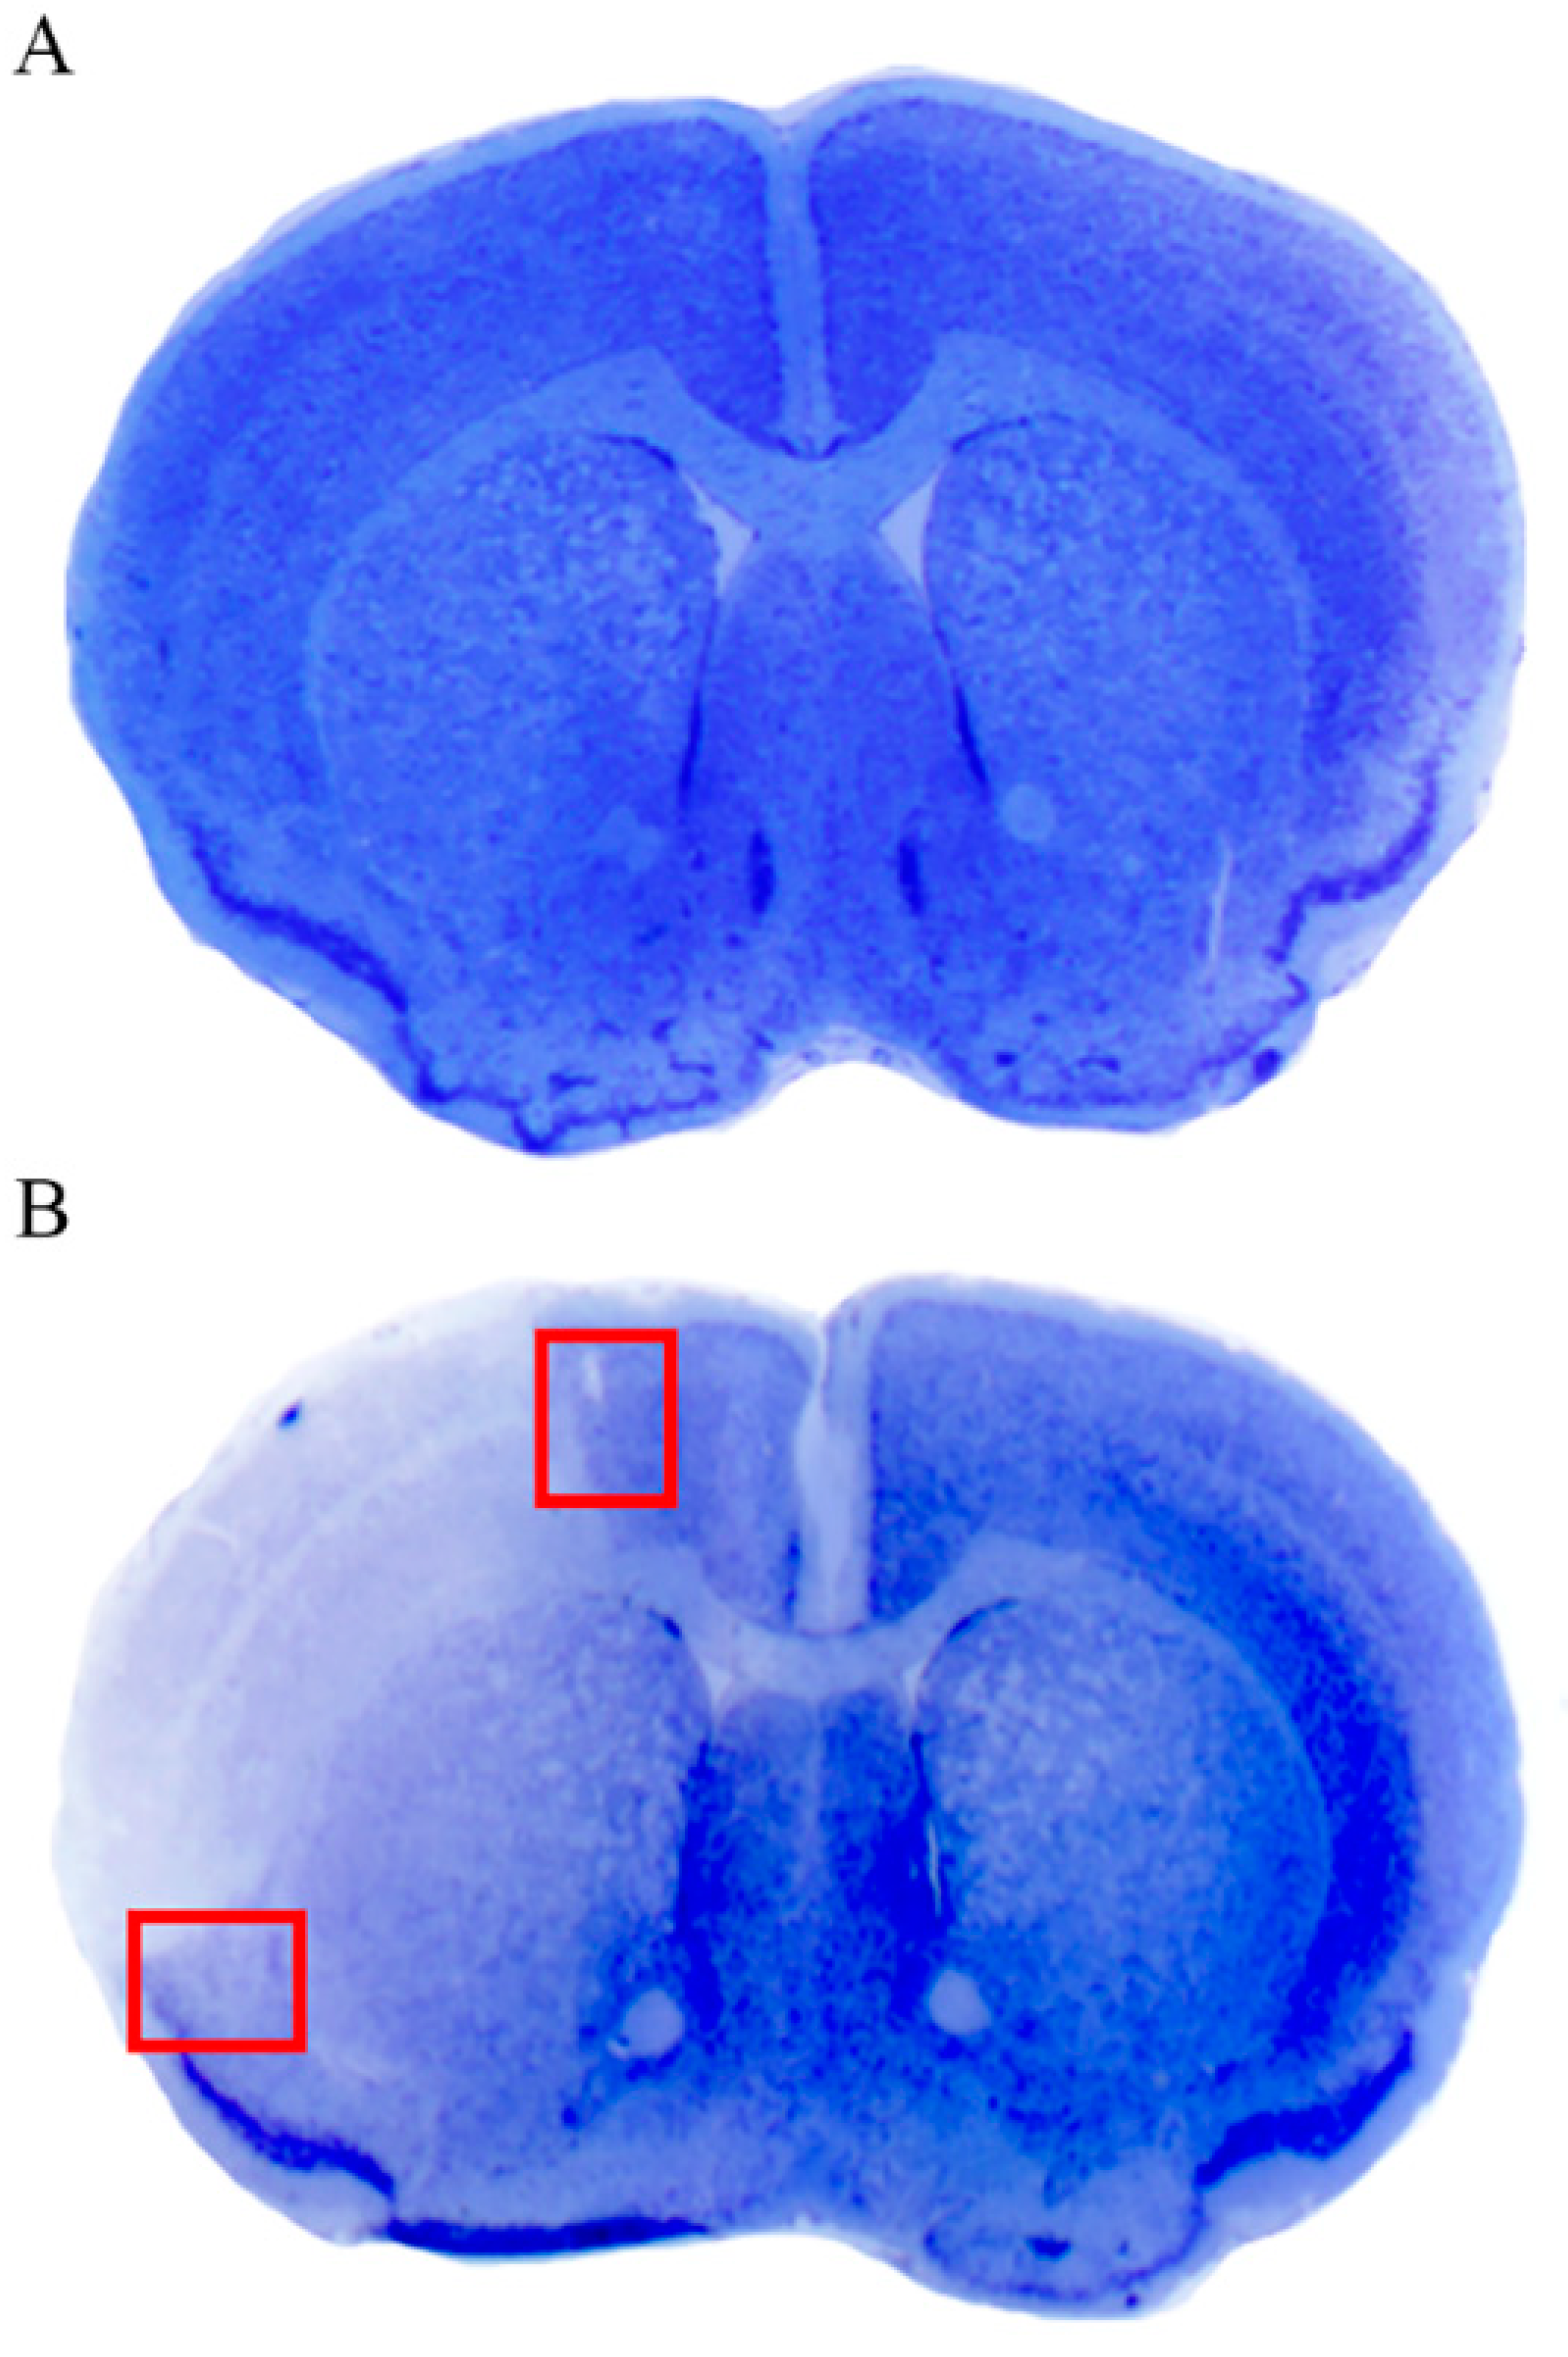

Following distal (Sylvian) occlusion of the middle cerebral artery (MCA), a wide permanent ischemic damage is produced in the ipsilateral hemisphere. This involves both cortical and sub-cortical regions (including the white matter and basal ganglia). As shown in Figure 3, the cortical peri-infarct area is evident following thionin staining as a region, where a sudden chromatic shift occurs from the abnormal pale necrotic tissue to the normal blue Nissl-stained brain matter. The cortical infarct area is well characterized as the pale region delimited by a dorsal and ventral peri-infarct area. The present study focuses on the peri-infarct region, as the presumed site of the area penumbra. Therefore, the cortical areas, which are selected for the anatomical study, correspond to those delimited by red squares of Figure 3. These can be distinguished into a ventral (basal) region and a dorsal (apical) region (Figure 3B). Some differences between dorsal and ventral regions were recently noticed [2]. These are likely to rely on a different vulnerability to ischemia of ventral allo-cortical (more damaged) compared with dorsal iso-cortical (less damaged) neurons [2]. Nonetheless, changes produced by ischemic damage are qualitatively similar within the dorsal and ventral regions. Thus, data from the ventral areas are included in the main body of the text, while data from the dorsal areas (largely confirmatory) are reported in the Supplementary Figures S2–S6.

As shown in representative Figure 3, the cortical peri-infarct area is evident following thionin staining as a region, where a sudden chromatic switch from the pale white frankly necrotic area to the blue normal Nissl-stained brain matter takes place. The cortical infarct area is well characterized as the pale region delimited by a dorsal and ventral peri-infarct area. Since the study focuses on the peri-infarct region as the presumed site of area penumbra, the cortex being analyzed for morphology is restricted to the area delimited by the red squares of Figure 3. Analogous regions were selected from the contralateral hemisphere and from corresponding cortical regions from sham-operated mice. Within these borderline regions, whole slices were cut for immunofluorescence; small fragments within these red squares were further dissected for electron microscopy and ultrastructural stoichiometry.

Figure 3. Thionin staining shows a pale ischemic brain area following middle cerebral artery occlusion (MCAO). (A) shows representative thionin staining from a sham-operated mouse, following the surgical procedure without occlusion of the middle cerebral artery (sham-operated, sham). (B) is a representative thionin staining from a mouse following right MCAO. The pale cortical and sub-cortical areas represent ischemic regions. In (B), red squares indicate the dorsal and ventral peri-infarct regions, which were selected for anatomical studies of the area penumbra.